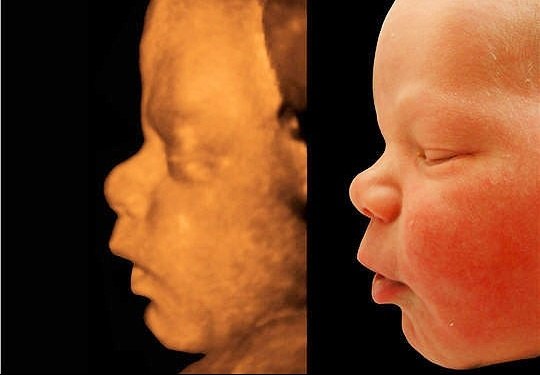

Также на экране во время осмотра можно разглядеть лицо ребенка и получить первый снимок.

- трехмерное УЗИ: новый способ исследования ультразвуком, который проводится с 23 недели беременности. Изображение трехмерного типа помогает выявить ошибки в диагностировании, которые возможны при двухмерной картинке. На экран выводится голограмма в цвете, которая позволяет рассмотреть даже мимику ребенка. Главный плюс данного исследования — это высокое качество картинки при безопасной длине волн. По времени трехмерное обследование проводится в два раза дольше, чем обычное;

- четырехмерное УЗИ: популярная диагностика, которая проводится на последних сроках беременности и позволяет получить детальное изображение малыша. В процессе исследования можно просмотреть движение плода, сделать видеозапись и фотографии.

Четырехмерное УЗИ